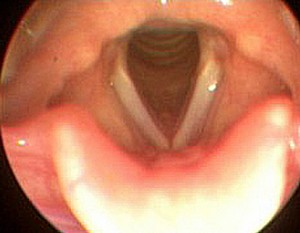

Stembanden in het strottenhoofd:

Gezonde stembanden:

Gesloten en open stembanden: